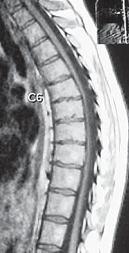

МРТ № 52

Иллюстрация к книге — Остеохондроз для профессионального пациента [i_083.jpg]

МРТ № 51

Иллюстрация к книге — Остеохондроз для профессионального пациента [i_084.jpg]

На МРТ № 51 наблюдается грудной отдел позвоночника с нормально выраженным физиологическим кифозом, межпозвонковыми дисками и спинным мозгом.

На МРТ № 52 наблюдается усиление грудного кифоза (гиперкифоз), снижение высоты межпозвонковых дисков с деформацией замыкательных пластин, расширением тел позвонков в вершине кифоза и самое главное — перерастяжение и уплощение спинного мозга на уровне вершины искривления.

Рассмотрим вариант нормы и патологии грудного отдела позвоночника (МРТ № 51, МРТ № 52). Конечно, заболеваний, которые могут проявиться вследствие развития остеохондроза грудного отдела позвоночника, достаточно. В каждом отдельном случае необходимо установить точный диагноз, осуществить грамотный подход в выборе методов лечения. Нельзя недооценивать возможные вариации развития заболевания. Вот, например, из-за таких деформаций позвоночника, которые можно наблюдать на МРТ № 52, порой возникают парезы или параличи, зачастую вследствие развивающегося ишемического «миелита», точнее спондилогенной миелопатии — перерождение вещества спинного мозга из-за недостаточного кровоснабжения. Причём то же клиническое течение спондилогенной миелопатии может протекать двояко. Чаще заболевание развивается исподволь, постепенно в течение довольно длительного времени. Порой останавливается, так и не достигнув своего апогея. А бывает (хотя и намного реже) в течение относительно короткого отрезка времени, на фоне полноценной функции спинного мозга, возникают парезы и параличи. Что лежит в основе этого тяжелейшего осложнения — спондилогенной миелопатии? Как правило, расстройство кровоснабжения спинного мозга. Оно, в свою очередь, возникает вследствие нарушения проходимости питающих его артериальных кровеносных сосудов. Опасность здесь таится в том, что значительный по длине спинной мозг, занимающий почти всю протяжённость позвоночника, получает кровоснабжение всего из нескольких артерий. Если даже одна из таких питающих артерий вследствие перерастяжения или сдавления «закупоривается», то значительные территории спинного мозга лишаются кислорода, питательных и других веществ, что приносит с собой его тканям артериальная кровь. Нарушение проходимости питающих спинной мозг кровеносных сосудов возникает вследствие их перерастяжения вместе со спинным мозгом и его элементами, что или приводит к сужению просвета растянутого артериального ствола или к прямому сдавлению его деформированными костными структурами позвоночника. Нервная ткань спинного мозга очень чуткая к недостаточности кровоснабжения и быстро гибнет в условиях неполноценного притока артериальной крови. Это, в свою очередь, приводит к возникновению частичных и полных параличей тех органов, которые зависят от поражённых территорий спинного мозга. Вот такая выстраивается цепочка, где одно событие неумолимо порождает другое и приводит к определённым последствиям.